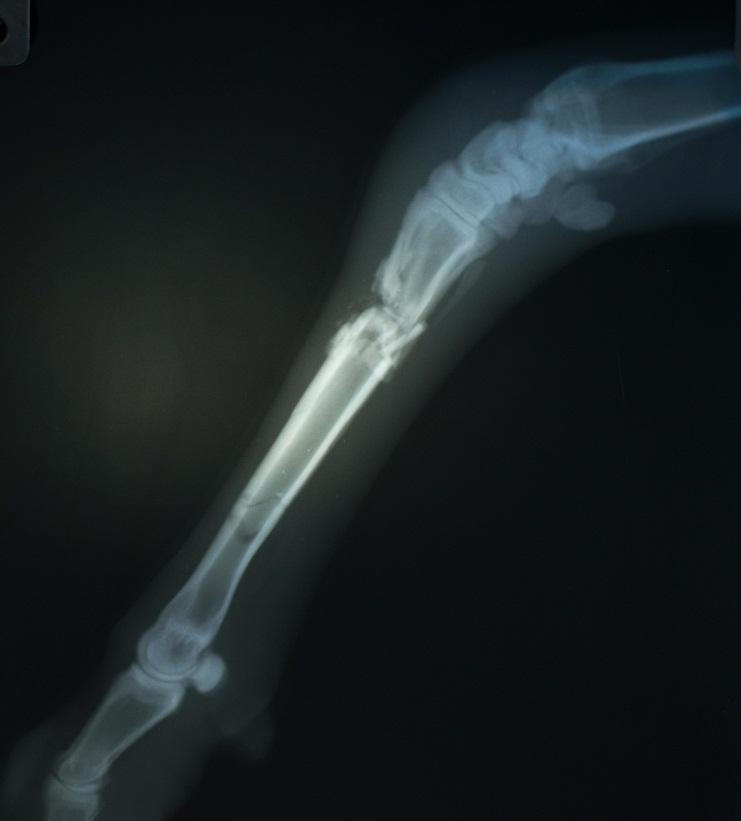

Использование аппарата наружной фиксации при лечении перелома у овцы

искривление конечности